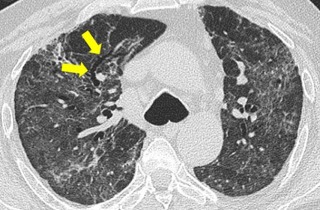

Medical News: A Growing Global Lung Health Crisis Chronic Obstructive Pulmonary Disease, commonly known as COPD, is a long-term lung condition that makes breathing progressively more difficult. It affects hundreds of millions worldwide and is already one of the leading causes of death. Current treatments mainly ease symptoms and slow progression, but they do not fully stop lung damage. This has p...

Medical News: A groundbreaking study has revealed that blocking a little-known bacterial peptide in the lungs can quickly reduce inflammation and scarring in advanced pulmonary fibrosis, a disease that is often fatal and has limited treatment options. The findings offer fresh hope that even late-stage lung fibrosis may still be biologically reversible when key disease drivers are targeted early en...